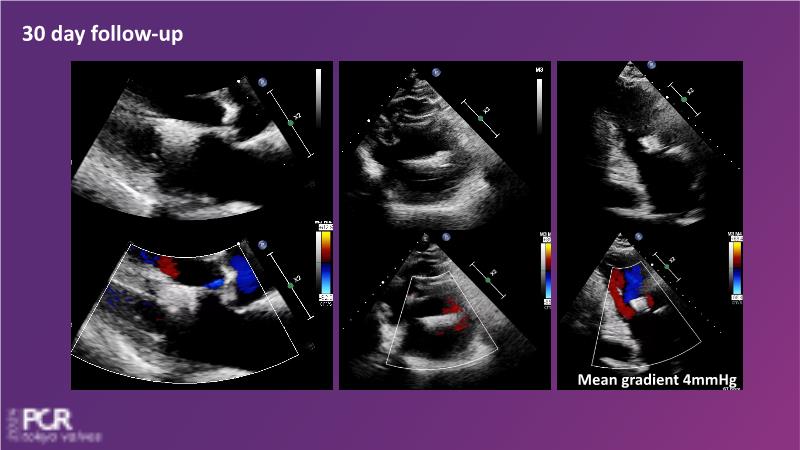

Watch this session to get an overview of a new TEER device, follow the step-by-step procedure related to initial experiences with this device for a Japanese patient with degenerative mitral regurgitation, learn about the latest data from RCT and registries, and follow discussions of challenging TEER cases!

- To learn procedural step-by-step of novel device